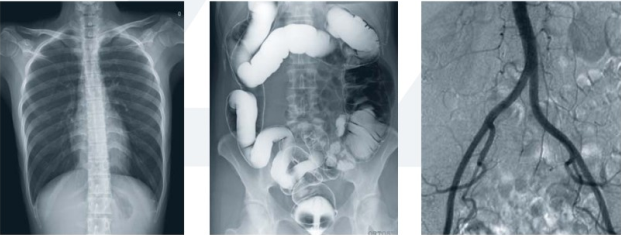

胃腸造影離不開(kāi)現(xiàn)代化的數(shù)字化胃腸顯影方式(一類(lèi)運(yùn)用常規(guī)胃腸機(jī)達(dá)到檢查目的;另一類(lèi)則運(yùn)用新推出的動(dòng)態(tài)DR達(dá)到檢查目的),它是一種能通過(guò)造影診斷用來(lái)檢查胃腸道疾病的X線(xiàn)檢查設(shè)備,是檢查各種潰瘍、腫瘤及異物等疾病的主要檢查方法之一。

隨著動(dòng)態(tài)DR的這股旋風(fēng)的盛起,部分胃腸機(jī)廠家也開(kāi)始大勢(shì)宣傳其胃腸設(shè)備同樣具備動(dòng)態(tài)功能。不過(guò)從市場(chǎng)的綜合反饋來(lái)看,雖然胃腸機(jī)在影像診斷上相比以前的醫(yī)療設(shè)備都有了較大的進(jìn)步,但和真正意義上的動(dòng)態(tài)DR依舊有一定的差距。

為什么目前市場(chǎng)上有很多客戶(hù)意愿選擇動(dòng)態(tài)DR這么一款多功能的產(chǎn)品作為替代胃腸機(jī)的一類(lèi)放射設(shè)備頭一個(gè)選擇,有哪些優(yōu)勢(shì)呢?常規(guī)胃腸機(jī)和動(dòng)態(tài)DR對(duì)比優(yōu)劣勢(shì)如下:

動(dòng)態(tài)DR胃腸造影檢查和消化內(nèi)鏡相輔相成,在胃腸道疾病的診斷方面具有其他檢查方法無(wú)可比擬的優(yōu)勢(shì)。僅在考慮特異性、適用性、普遍性的胃腸檢查上不難發(fā)現(xiàn),動(dòng)態(tài)DR胃腸造影檢查略有優(yōu)勢(shì)。特別是疑難病例上,全面分析胃腸大概狀況,離不開(kāi)造影的有效應(yīng)用。

同時(shí), 動(dòng)態(tài)DR的應(yīng)用實(shí)現(xiàn)了狀態(tài)和功能同時(shí)記錄觀察,既可留下大量的資料,又拓寬了檢查范圍,對(duì)臨床工作者的使用慣性和操作都有不可替代的地位。

但是,要保障胃腸道檢查的“準(zhǔn)確高效”,多元化的診療方案提出和施行無(wú)可厚非!對(duì)于老百姓,對(duì)于一線(xiàn)的臨床工作者,“不斷優(yōu)化選擇成像方式和技術(shù)參數(shù),不斷合理應(yīng)用后處理技術(shù),不斷積極開(kāi)展新技術(shù),不斷設(shè)法降低X線(xiàn)輻射劑量”“四個(gè)不斷”會(huì)讓病變顯示率進(jìn)一步提高,讓臨床應(yīng)用價(jià)值進(jìn)一步得到體現(xiàn)。